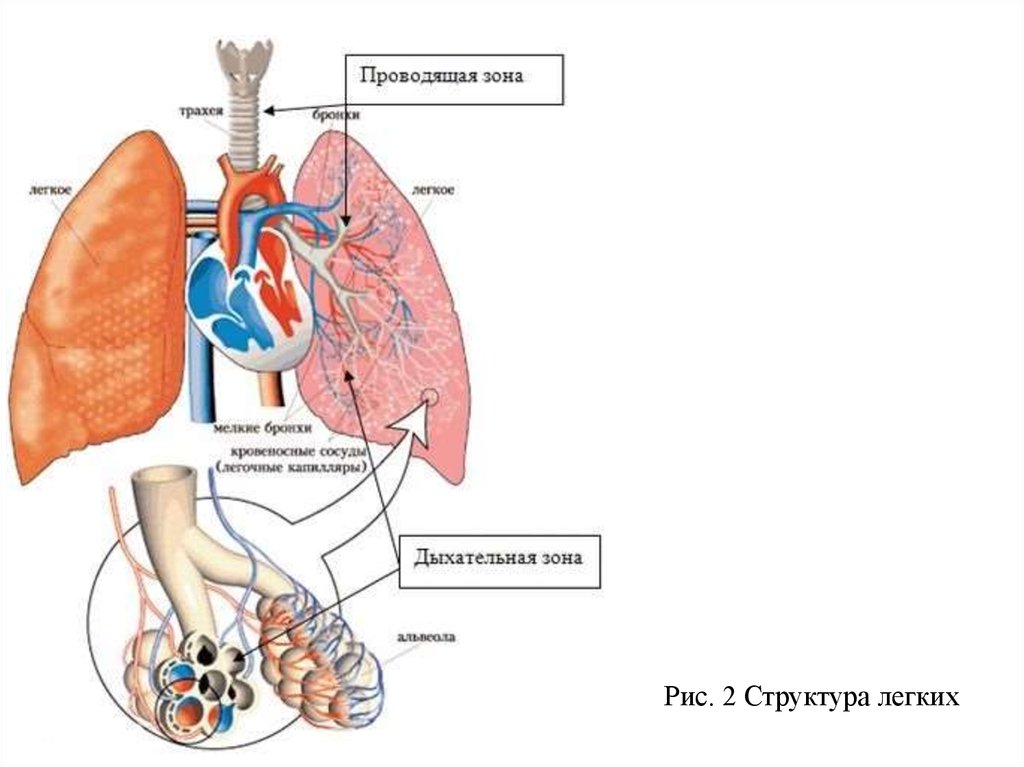

Роль легких в метаболических процессах